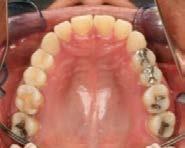

En los estudios intraorales de inicio en las fotografías se muestra en la de frente el diastema anterior, con la línea media dental superior e inferior no coincidentes, la mordida profun da anterior (Figura 2), en la lateral derecha clase l molar y canina bila teral (Figura 3), el apiñamiento leve superior e inferior y la forma de las arcadas.

En la radiografía panorámica se observa 28 piezas dentales, con un diastema en los incisivos centrales (Figura 5).

Figura 1. Extraoral de inicio de frente. Figura 2. Intraoral de frente derecha, izquierda. Figura 3. Oclusal superior e inferior arcadas cuadrada. Figura 4. Radiografía lateral de cráneo. Figura 5. Rx Panorámica.